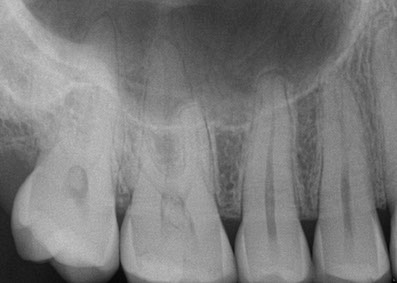

• Diagnostic X-rays